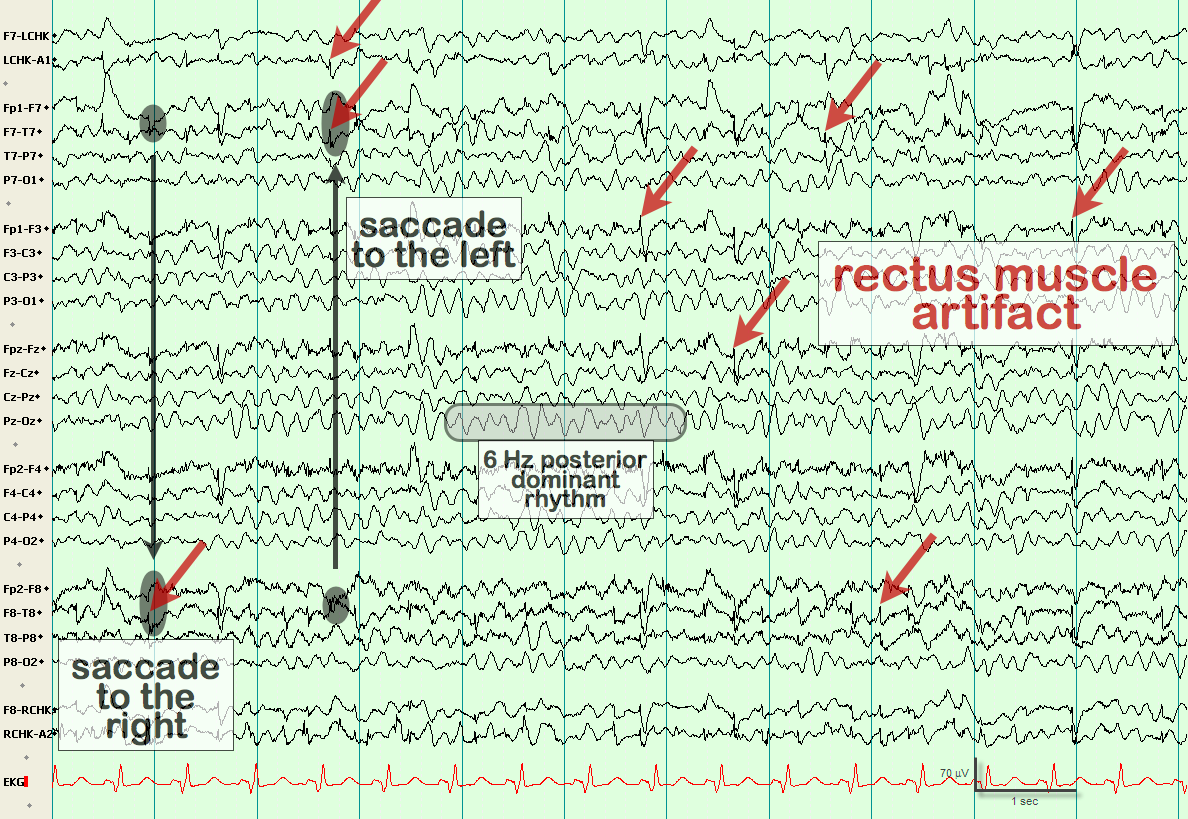

| Lateral Eye Movements And Eye Blinks Recorded Simultaneously With

www.researchgate.net

www.researchgate.net

movements blinks recorded simultaneously eog bipolar

Lateral Eye Movement Although A Horizontal, Frontal Dipole Is The Key

www.pinterest.com

www.pinterest.com

eye movement eeg lateral horizontal key bullet journal

Lateral Eye Movement

eegatlas-online.com

eegatlas-online.com

artifacts eye movement lateral eegatlas online

Lateral Eye Movement

eegatlas-online.com

eegatlas-online.com

eye lateral movement artifacts eegatlas online

Lateral Eye Movement

eegatlas-online.com

eegatlas-online.com

artifacts eye movement lateral eegatlas online

Lateral Eye Movement

eegatlas-online.com

eegatlas-online.com

eye movement lateral artifacts online eegatlas